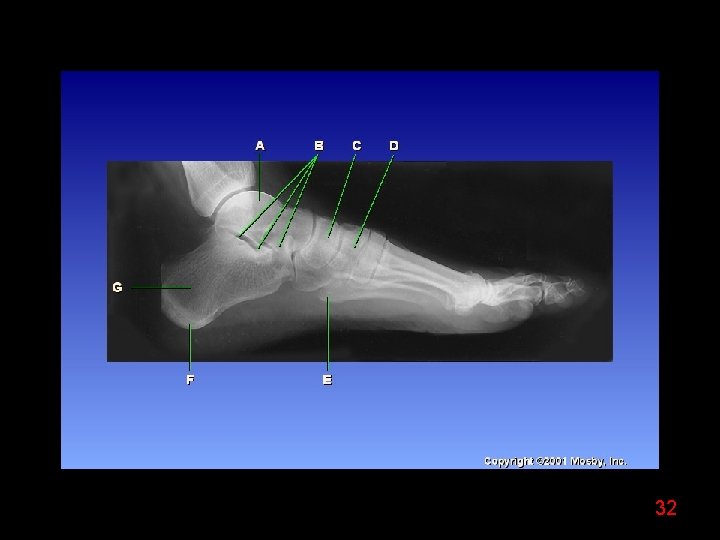

32

33